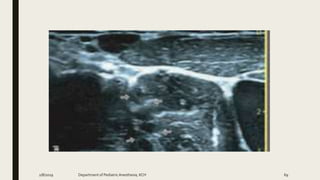

QL BLOCK

2/8/2019 Department of PediatricAnesthesia, KCH 96